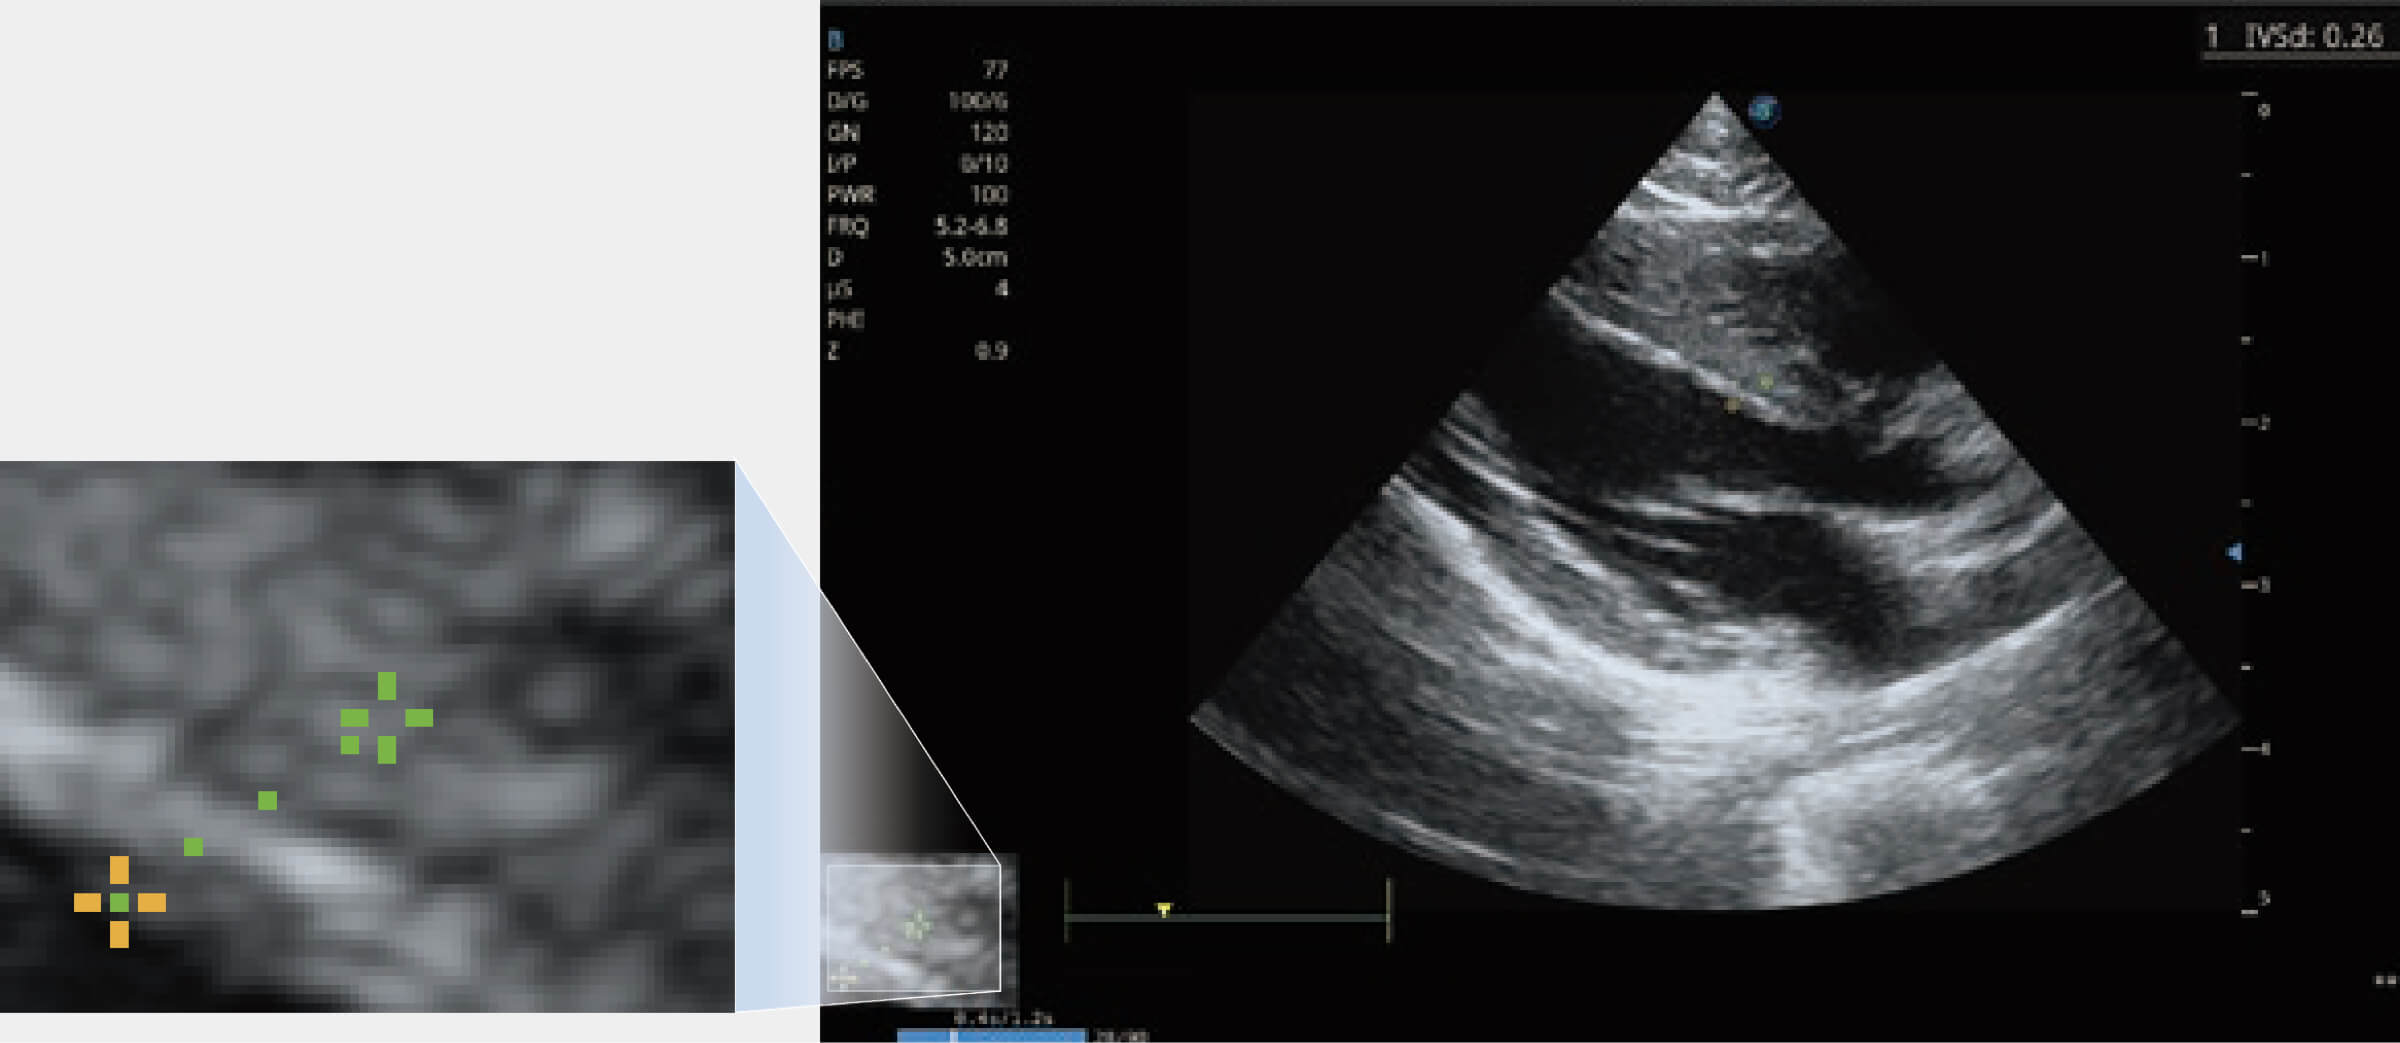

ProPet 70 进一步提升了微米成像算法,更加注重对基础原始图像的还原和保留,在有效减少斑点噪声、增强组织边界显示的同时,避免过度优化丟失真实的解剖信息。

能够基于左心室壁追踪和辛普森法,自动计算射血分数,支持多个可移动点描迹,与手动测量相比,极大节省了动物医生的时间和精力。

通过360度任意调节3条M型取样线,在同一心动周期上观察心脏不同位置的运动曲线,得到准确的心功能测量数据,有效评估心肌运动及左心室功能。

实时用颜色表示心肌组织运动,观察和定量组织的运动情况,对快速检测与评估心肌的灌注和活性、电传导及心肌收缩和舒张功能等均能提供重要的诊断信息。